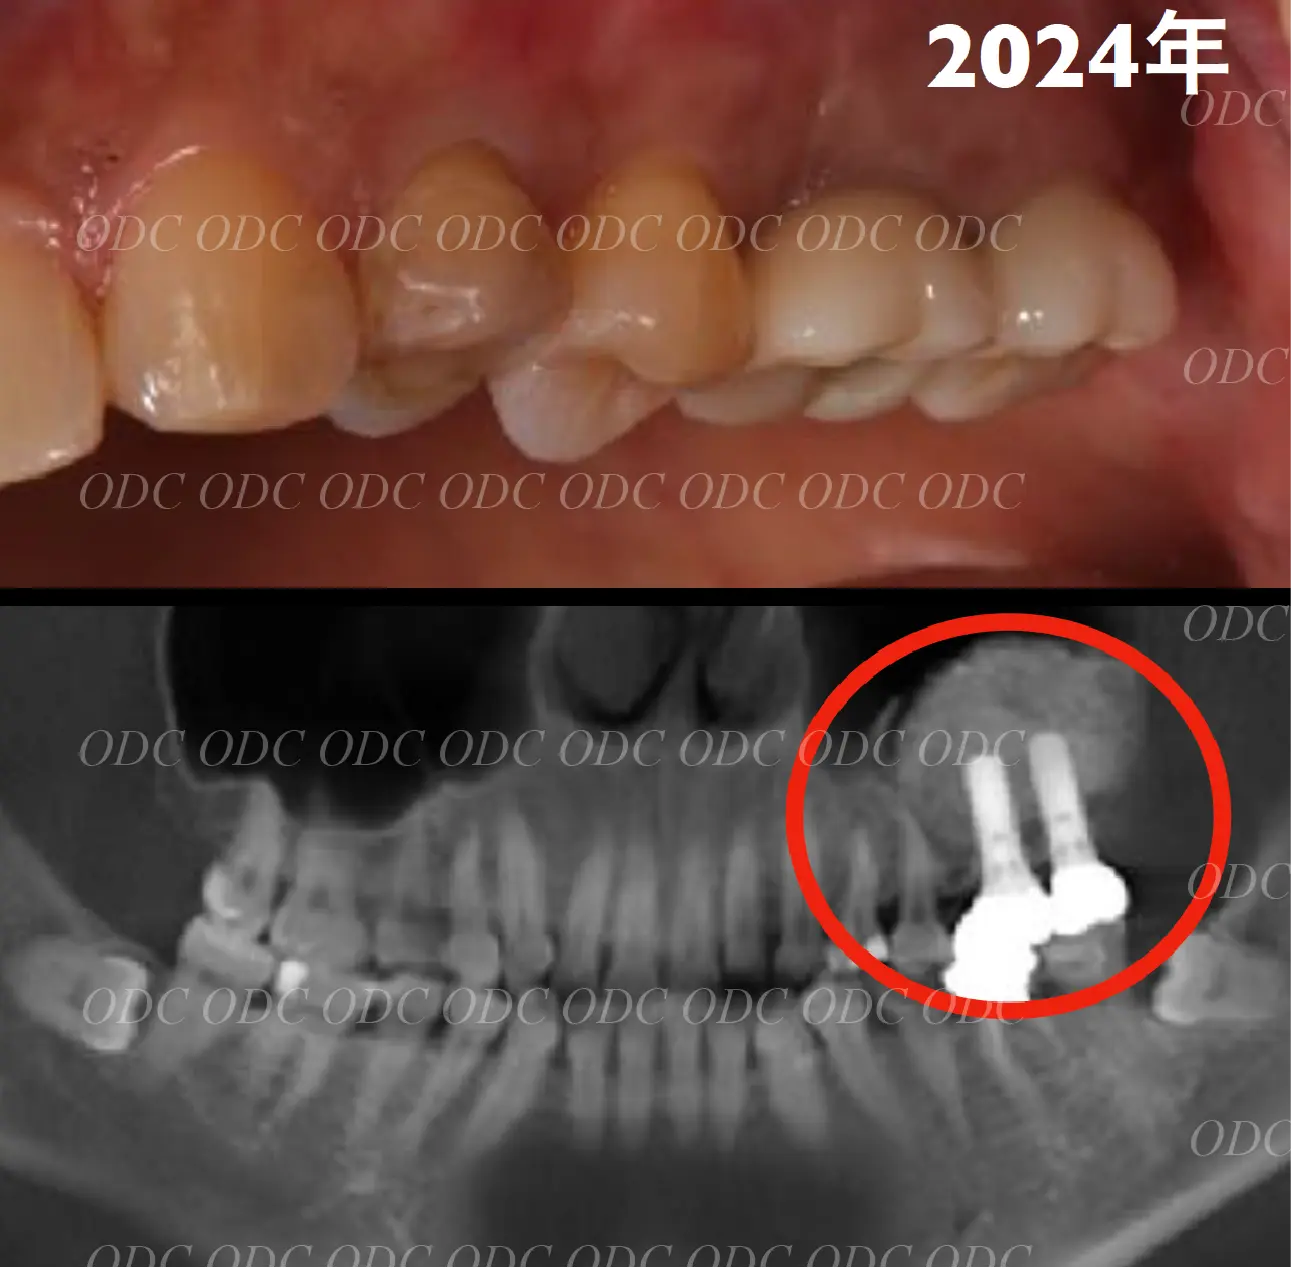

2024年、治療終了後約10年が経過いたしました。

顎関節を考慮した包括的な治療を行うことで咬合状態(噛み合わせ)は現在もとても安定した状態です。